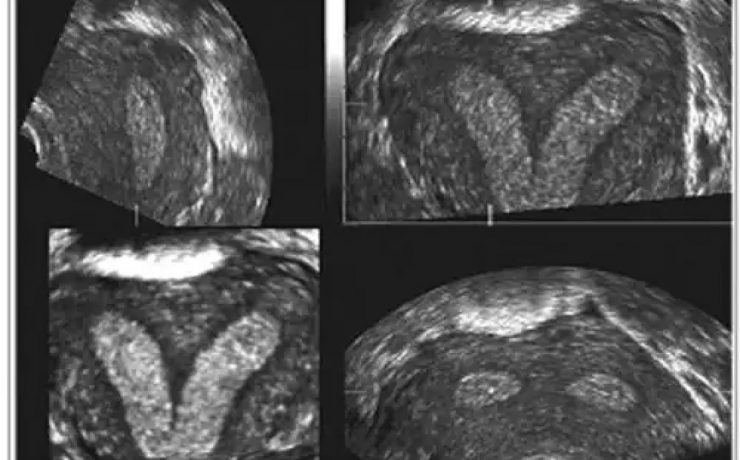

Este es un artículo de revisión publicado por el Departamento de Ginecología y Obstetricia del Hospital William Beaumont, Oaklahoma USA. La placenta accreta con sus variantes increta y percreta son una causa importante de hemorragia en el segundo y tercer trimestre de gestación representando hasta el 50% de las histerectomías